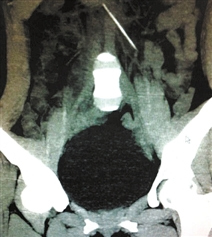

后来,医生又给小陈做了个三维CT,片子一出来,所有人都呆住了——小陈的肠子里,有一根牙签,长约五六厘米。

牙签一半插在肠子里,另一半插在十二指肠里,已经戳破了十二指肠壁。